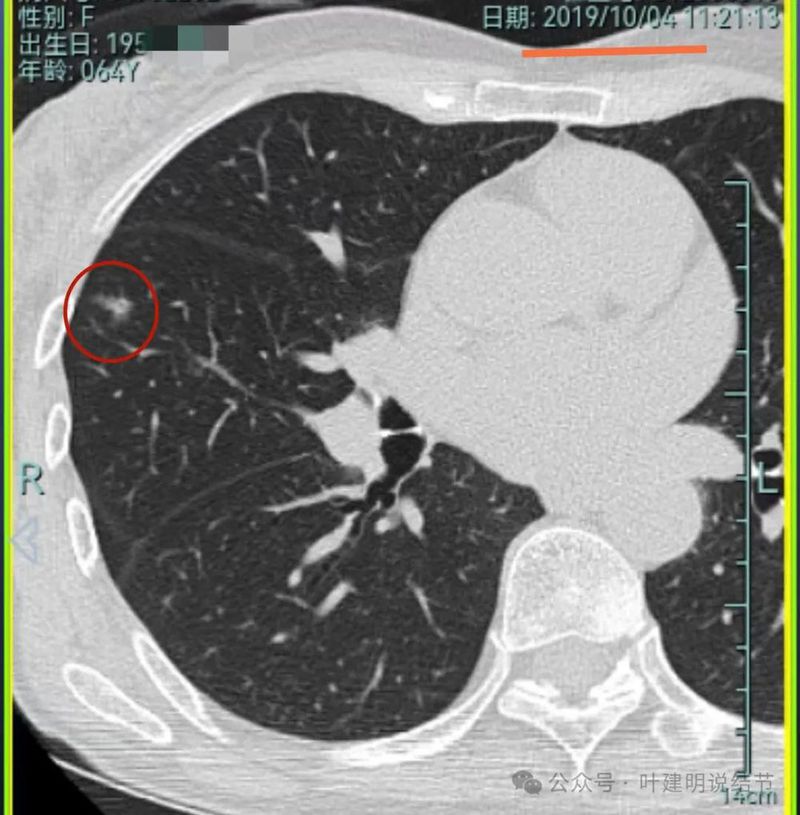

先来看2019年时的影像:

病灶6:左上叶淡磨玻璃结节,轮廓较清,密度较低。

病灶7:左下叶胸膜下结节,大部分磨玻璃密度,只是不太均匀,说不上明显的实性成分,整体轮廓与边界较清。此灶当年已经切除,从术后影像来看,大概是段切除可能性大些。